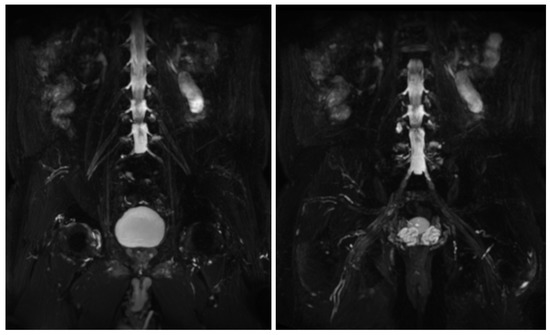

Figure 6.

MIP (Maximum Intensity Projection) reconstructions of the 3D cube nerve MR sequence of the lumbosacral plexus show regular size and signal intensity of lumbar and sacral roots.

MR findings: regular size and signal intensity of lumbar and sacral roots (Figure 6). Bilateral and symmetrical sciatic nerve T2 enlargement and fascicular hyperintensity (Figure 7). Mixed acute and chronic denervation of the muscles of the anterolateral compartment of the thigh. Mainly chronic denervation of the gluteal muscles (Figure 7).